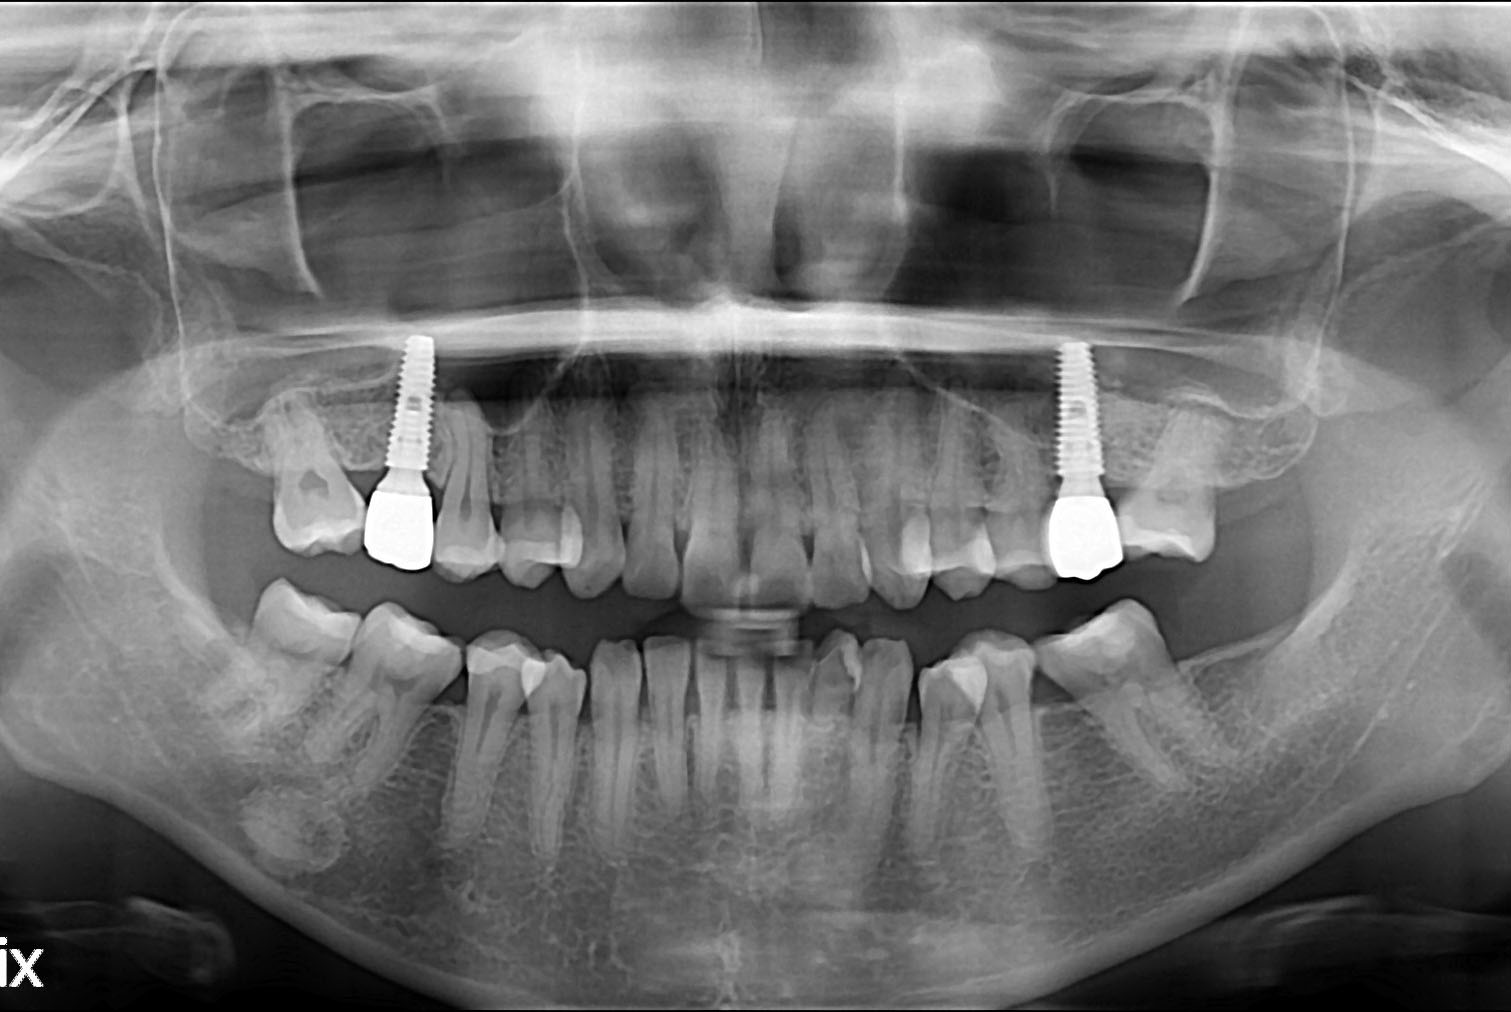

[임플란트] 임플란트

치료전 : 2019-06-17

세종치과는 많은 환자와 다양한 케이스를 바탕으로 항상 편안한 임플란트 수술을 제공하고자 노력하고,

오래동안 튼튼히 쓸 수 있는 임플란트 수술을 가장 큰 목표로 삼고 있습니다